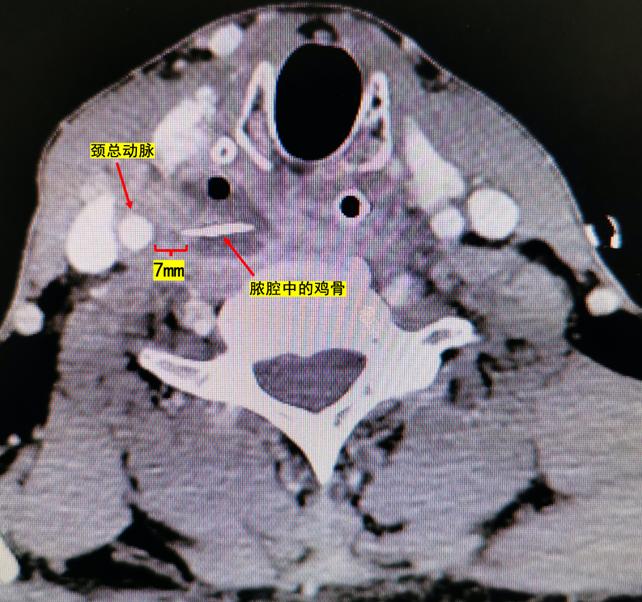

当地卫生院检查之后便立即建议金先生前往上级医院就诊。金先生先后辗转市级医院以及多家综合医院检查发现鸡骨头可能已经部分穿破到食道外面,但均未能取出。到我院就诊时,这枚鸡骨已经在金先生的颈部卡了4天,颈部的疼痛已经越来越剧烈,金先生出现了颈项强直体位,就连吞一口水都很困难,不敢吃饭,也睡不着觉。经我院头颈外科专家复查颈部增强CT,发现这根长约1.5cm的鸡骨头可能已经穿出食道到了右侧咽后及咽旁间隙,并且继发感染形成了明显的脓肿,最可怕的是这根鸡骨距离颈总动脉仅有约7mm的距离,如果鸡骨继续向外侧移位刺破颈总动脉就会引发致命的大出血!

在手术室麻醉科的通力配合下,准确定位脓腔,排出脓液,并从脓腔中顺利取出了这枚尖端锋利的“罪魁祸首”鸡骨。